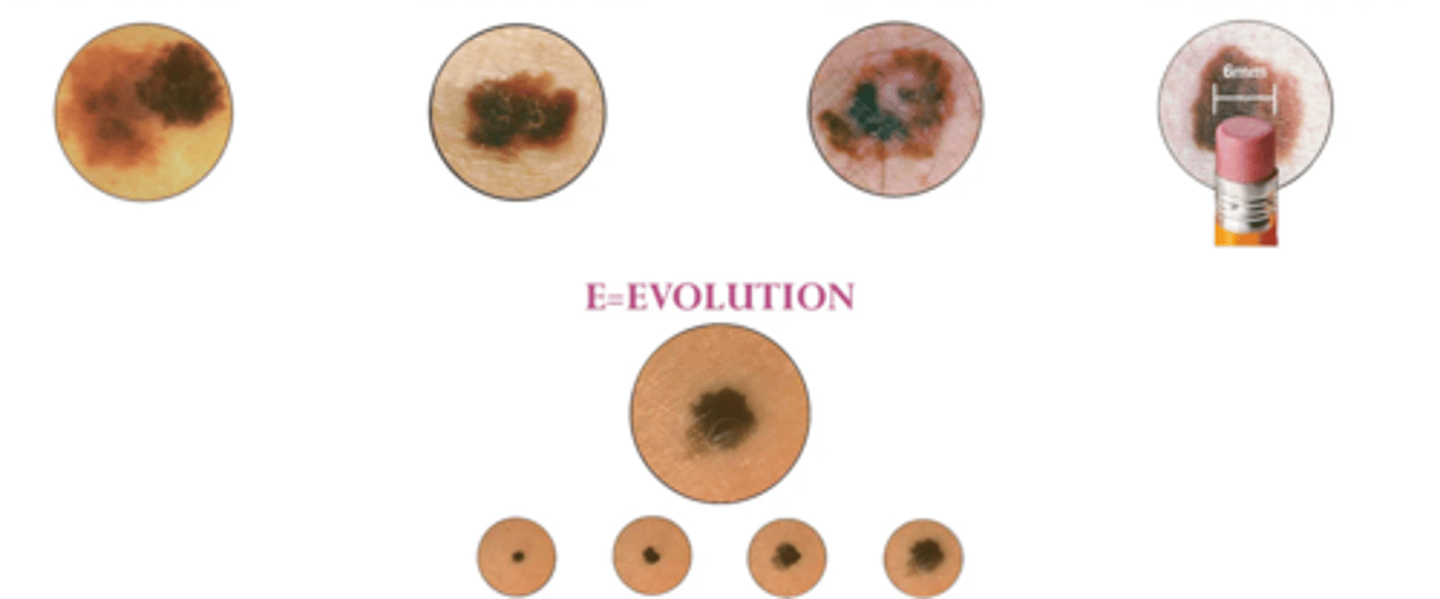

Melanoma

most aggressive/fast growing

least common

often fetal

Red flags of malignancy

Asymmetrical sides

Border has indentations

Color is black/brown/tan

Diameter larger than 6mm

Elevation